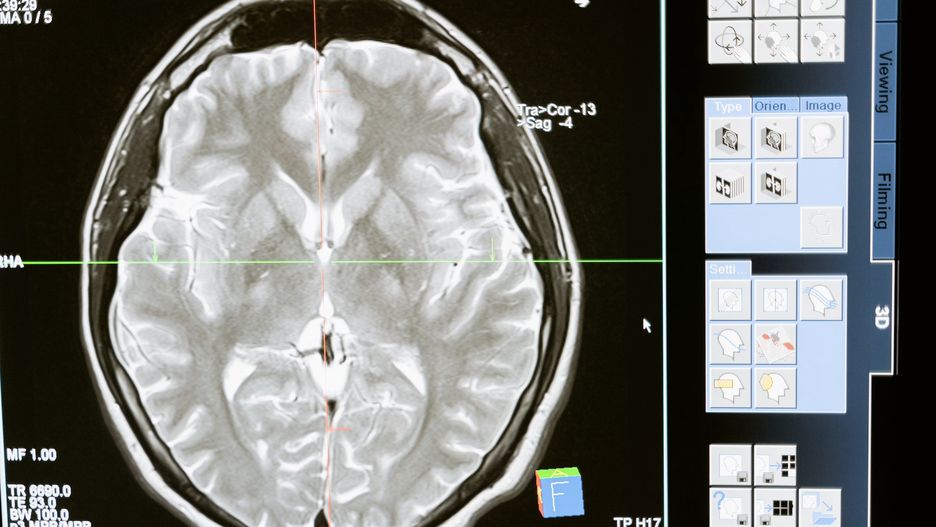

To, co zaraz przeczytacie, jest po prostu niesamowite. Podkreśla ogromny rozwój nauki, a zwłaszcza sztucznej inteligencji. Eksperci odtworzyli obrazy z mózgu myszy, której puszczali film. Efekt przeszedł ich najśmielsze oczekiwania i jest niezwykle dokładny. Czy niebawem będzie możliwe czytanie w myślach?

Narzędzie do odtwarzania obrazu na podstawie fal mózgowych przetworzonych przez sztuczną inteligencję opracował zespół badawczyEcole Polytechnique Federale de Lausanne. Imponująca nie tylko jest dokładność algorytmu, ale również to, że wszystko dzieje się w czasie rzeczywistym. Poniżej możecie zobaczyć na filmie mysz poddaną eksperymentowi.

Algorytm CEBRA został wytrenowany na podstawie analizy fal mózgowych, które płynęły podczas oglądania konkretnych obrazów. Na ich podstawie był w stanie przewidzieć i odtworzyć obejrzany przez gryzonia klip. Potocznie mówiąc – tak, program komputerowy wyczytał w myślach zwierzęcia to, co zobaczyło.

Klatka z filmu oraz odtworzony przez CEBRA obraz są niemal identyczne. Elektrody w mózgu myszy mierzące intensywność i charakter fal mózgowych sprawdziły się doskonale. Aż nie chce się wierzyć, że nauka doszła właśnie do poziomu tego, co wcześniej znaliśmy jedynie z filmów science-fiction. To już nie są wymysły ani wizje, a rzeczywistość.